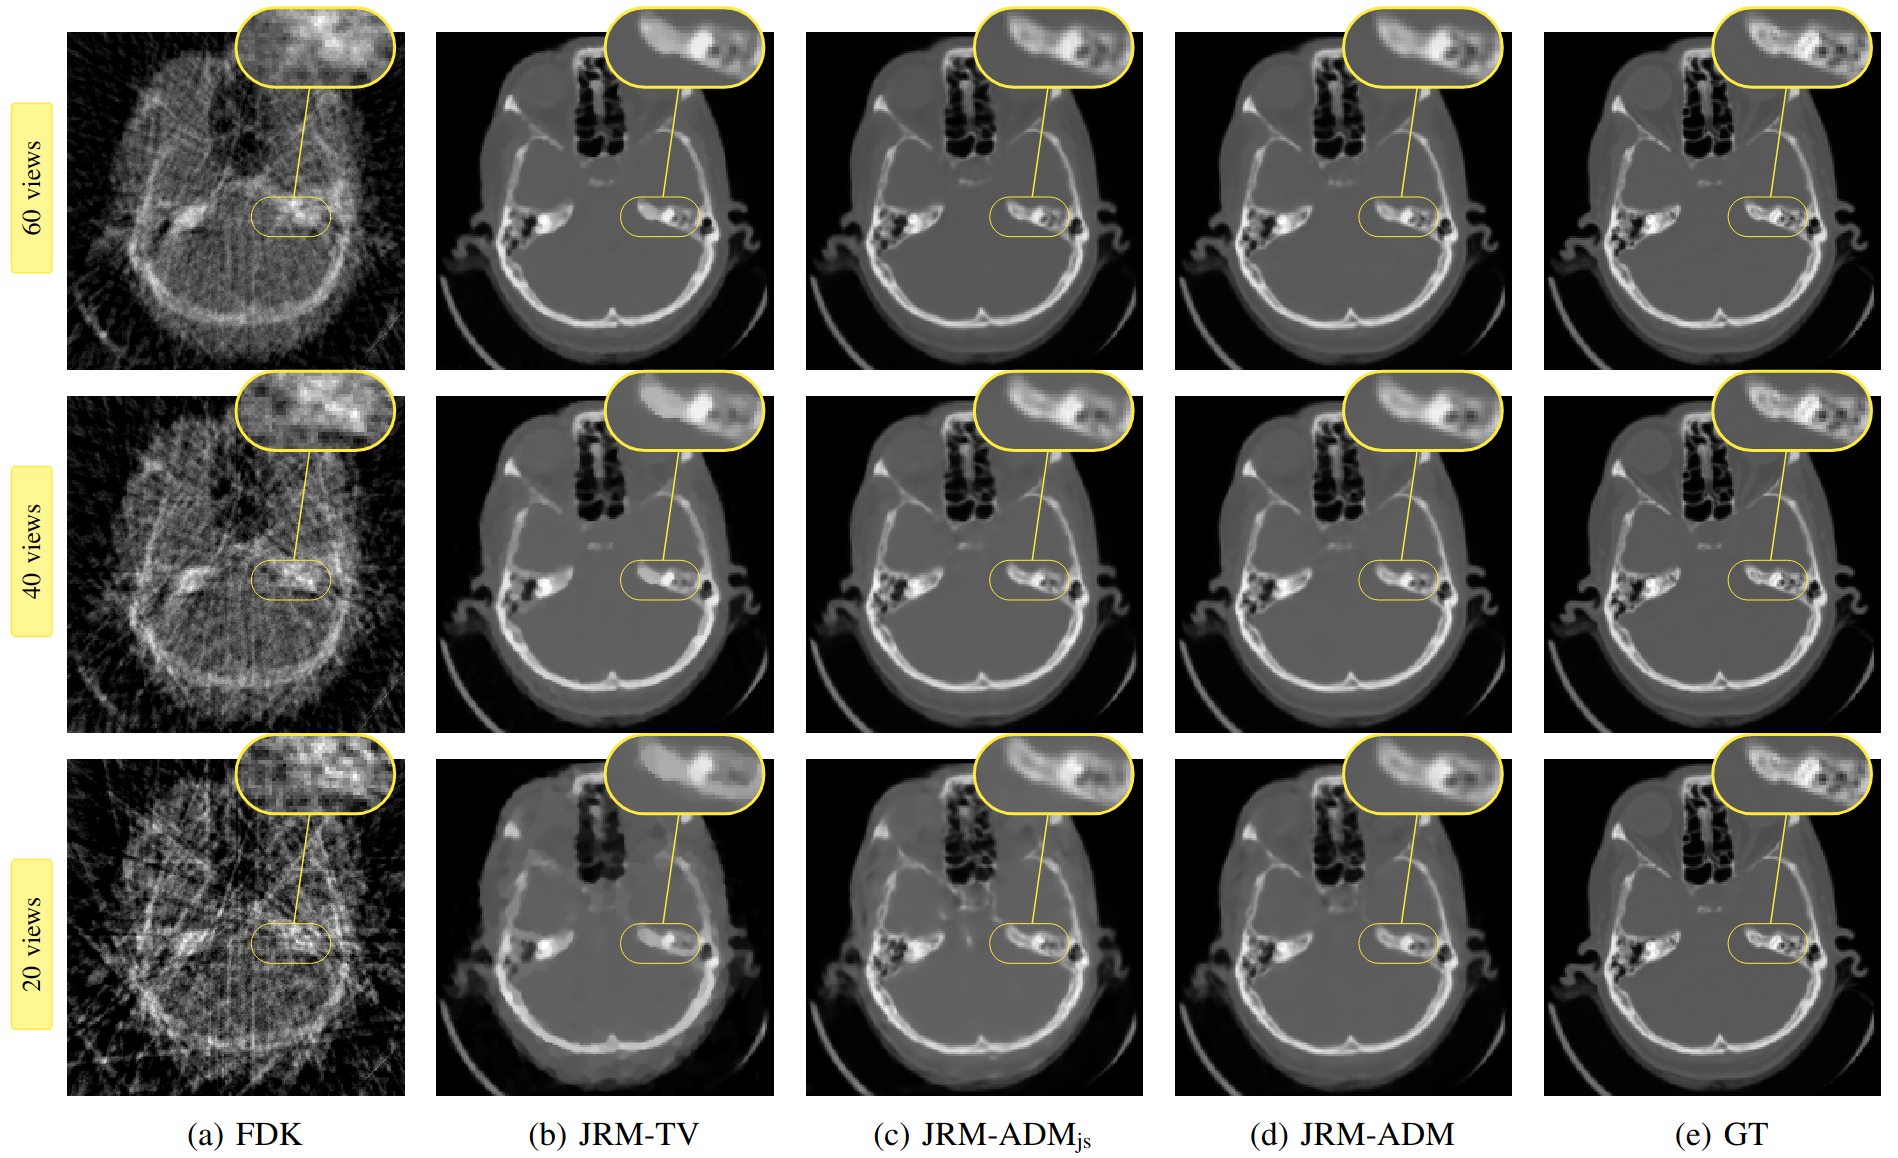

Figure 3: Ground truth and reconstructed volumes (axial plane) for motion affected sparse-view CBCT: results are shown for 60-, 40-, and 20-view acquisition settings.